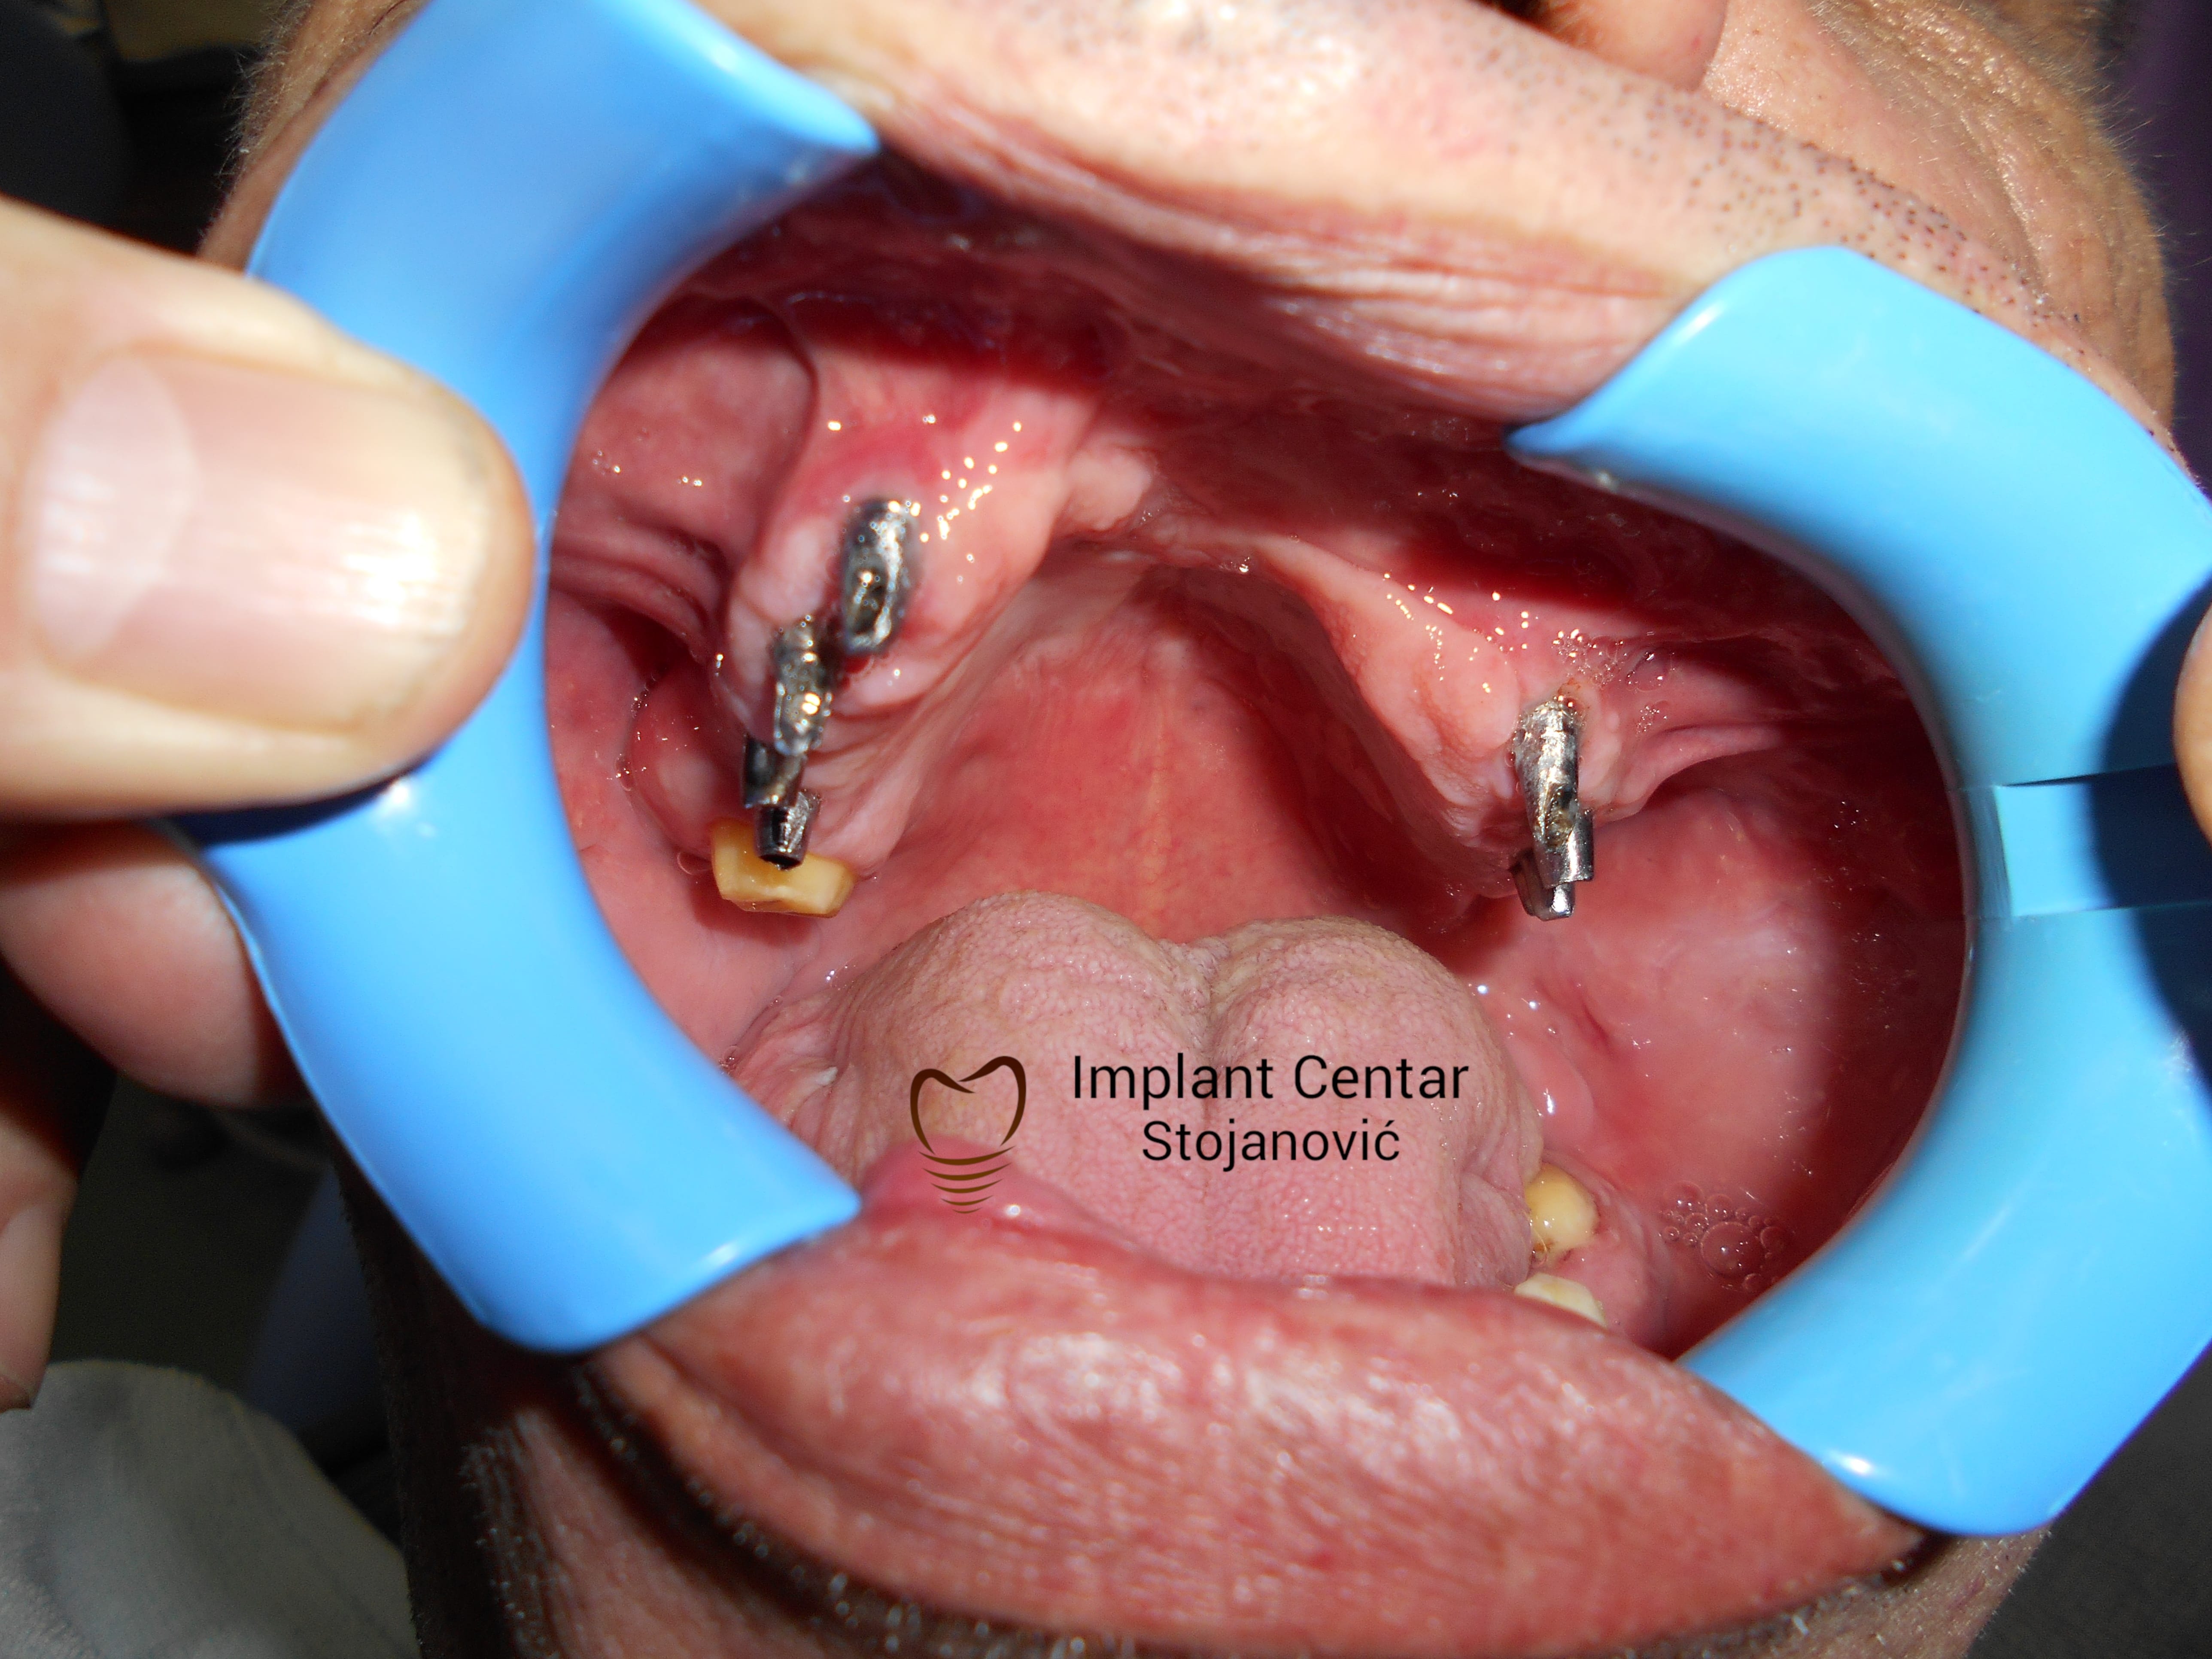

Implantno-protetska sanacija defekta gornje vilice uzrokovanog ratnom traumom

Pacijent iz USA sa ratnom traumom zadobijenom tokom rata u BiH Dum-Dum metkom.

PRISTUPILI SMO RESAVANJU DEFEKTA GORNJE VILICE SA CILJEM MAKSIMALNOG KOMFORA I SIGURNOSTI ZA PACIJENTA UGRADNJOM IMPLANTATA I IZRADOM FIKSNOG METALOKERAMICKOG MOSTA